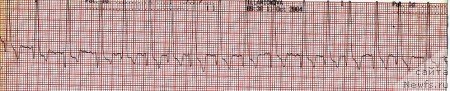

На поздних стадиях сердечной недостаточности у большинства собак появляются нарушения ритма. Наиболее частой аритмией является мерцание предсердий (мерцательная аритмия). Чаще всего она постоянна и имеет тахисистолическую форму (рис. 3).

Рис. 3. Тахисистолическая форма мерцательной аритмии.

Отдельную группу составляют собаки пород доберман пинчер и боксер, у которых ДКМП протекает с длительной скрытой фазой, составляющей иногда 2-3 года. В этот период единственным отклонением от нормы является нарушение ритма сердца. У доберманов чаще всего регистрируют левожелудочковую экстрасистолию и желудочковую тахикардию (рис.5). У боксеров экстрасистолы и тахикардия имеют проавожелудочковое происхождение (рис.4).

Рис. 4. Правожелудочковая тахикардия.

Рис. 5. Парные желудочковые экстрасистолы.